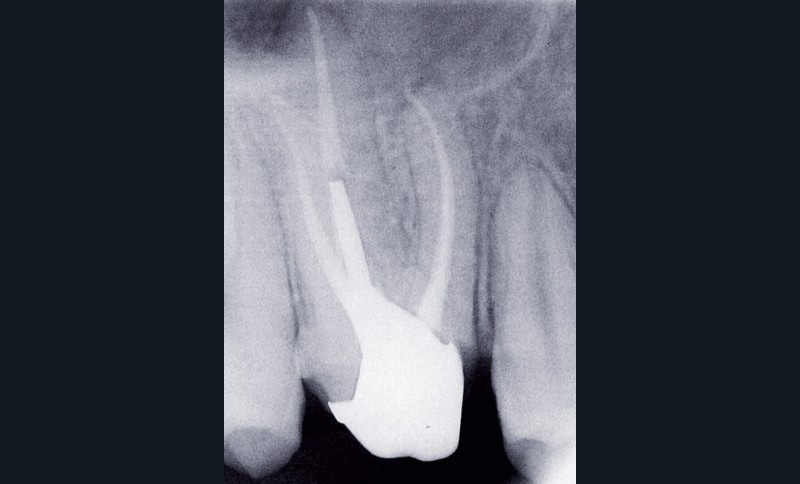

– obtention d’une étanchéité coronaire efficace le plus rapidement possible par le scellement d’un inlay-core et d’une couronne provisoire si les tissus dentaires résiduels sont insuffisants (fig. 1).

L’étanchéité des obturations coronaires provisoires et permanentes conditionne pour une grande part la réussite du traitement endodontique. Ainsi, en 1987, Swanson et Madison [42] ont montré qu’un traitement endodontique parfaitement réalisé était infiltré par des bactéries sur près de 85 % de sa hauteur entre 3 et 56 jours en l’absence de fermeture de la cavité d’accès endodontique. De la même manière, Torabinejad et coll. [44] ont étudié la pénétration de deux espèces bactériennes (Staphylococcus epidermis et Proteus vulgaris) au sein de canaux obturés par une technique de condensation latérale. Ils ont montré que dans plus de 50 % des canaux traités, les bactéries étaient retrouvées au niveau de l’apex 19 jours seulement après exposition à Staphylococcus epidermis et 42 jours après exposition de la cavité d’accès à Proteus vulgaris. Khayat et coll., en 1993 [12], ont montré qu’après 30 jours d’exposition à la salive naturelle, des bactéries étaient retrouvées au niveau apical pour l’ensemble des canaux traités.

En 1995, Ray et Trope [22] ont évalué radiographiquement sur près de 1 000 dents l’apparition ou non de lésions apicales selon les qualités de la restauration coronaire et de l’obturation canalaire. Les auteurs ont montré qu’un traitement endodontique de mauvaise qualité associé à une restauration coronaire de qualité donne de meilleurs résultats en termes de non-survenue d’une LIPOE qu’un traitement endodontique bien mené associé à une obturation coronaire défectueuse. Tavares et coll., en 2009 [43], confirment cette étude, en montrant que le taux de succès du traitement endodontique est plus élevé lorsque la restauration coronaire est de bonne qualité, et ce, indépendamment de la qualité du traitement endodontique.

Toutefois, la qualité d’une obturation coronaire, aussi bonne soit-elle, ne peut en aucun cas compenser un traitement endodontique de mauvaise qualité [45].